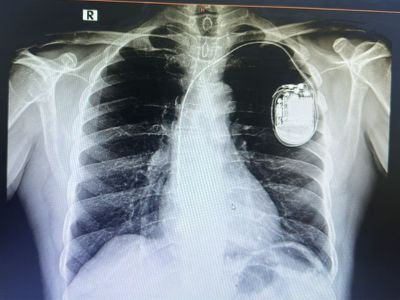

Pacemakers (Single/Dual)

Pacemakers help your heart beat at a normal, steady pace when it becomes too slow or irregular. A single pacemaker works with one chamber of the heart, while a dual pacemaker supports two. These devices keep your heartbeat stable so you can stay active, comfortable, and safe in daily life. Here’s how to know that you need a pacemaker.

Pacemaker implantation is a minor procedure where a small device is placed under the skin to regulate your heartbeat and improve cardiac rhythm.